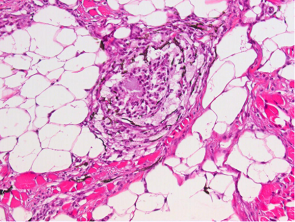

Prevalensen av svarte flekker hadde en økende trend gjennom forsøket. Siste uttak var 14 måneder etter sjøutsett. Ved mikroskopi ble det klart at det er en stor variasjon av vevsforandringer innen kategorien «svarte flekker», alt fra upåviselige forandringer til kraftige betennelsesforandringer som vi har beskrevet før. Forandringene kunne finnes med og uten pigmenterte celler. Dette viser at noe som man tror er en melaninflekk ikke nødvendigvis er det. Tvert imot kunne slike flekker bare inneholde gammelt bindevev og ikke være gjenstand for noen betennelse. Da er det trolig at lysbrytninger i bindevevet kan medføre at man oppfatter det som en melaninflekk mens det i virkeligheten er gammelt arrvev. Disse funnene viser at beskrivelser og registreringer av svarte flekker alltid må følges av en histologisk karakterisering. Utover i forsøksperioden endret de svarte flekkene både karakter og ble mer uttalte og alvorlige observert ved obduksjon av fisken og i mikroskop. I disse mest uttalte og alvorlige svarte flekkene med betennelse ble det alltid funnet PRV, og det var det eneste infeksiøse agens som ble funnet i denne studien.